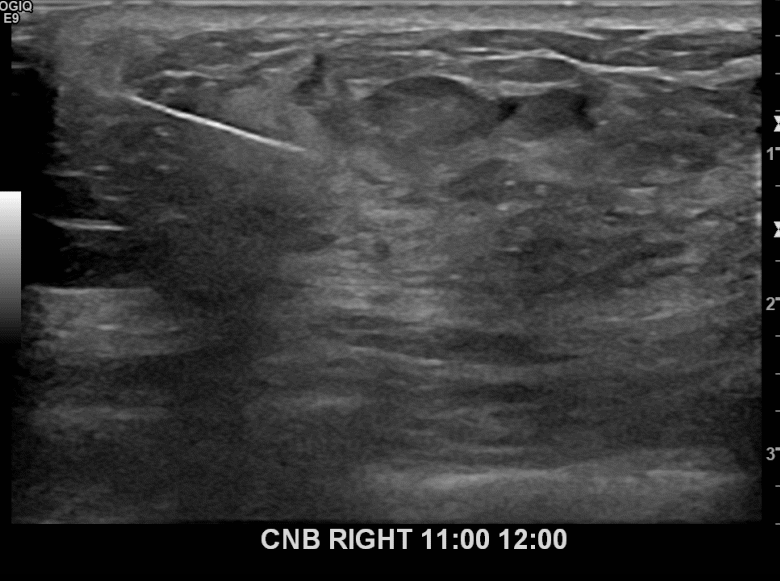

아산유외과개원후 677번째 유방암진단

상기환자 외부검사상 이상소견으로 내원하신 60대여성으로 우측에 의심스러운혹 조직검사시행해 유방암 진단되었습니다.